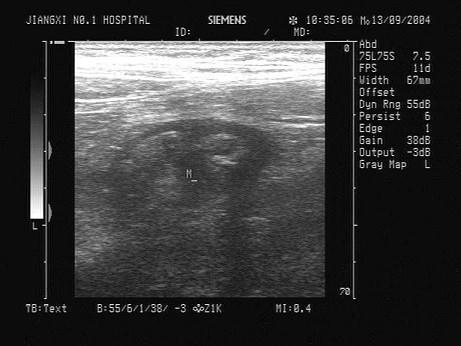

患者,右下腹压痛反跳痛。结合超声声像图,最可能的诊断是?(?)A.肠梗阻B.结肠癌C.正常阑尾D.阑尾炎E.肠穿孔

选项 A.肠梗阻 B.结肠癌 C.正常阑尾 D.阑尾炎 E.肠穿孔

答案 D